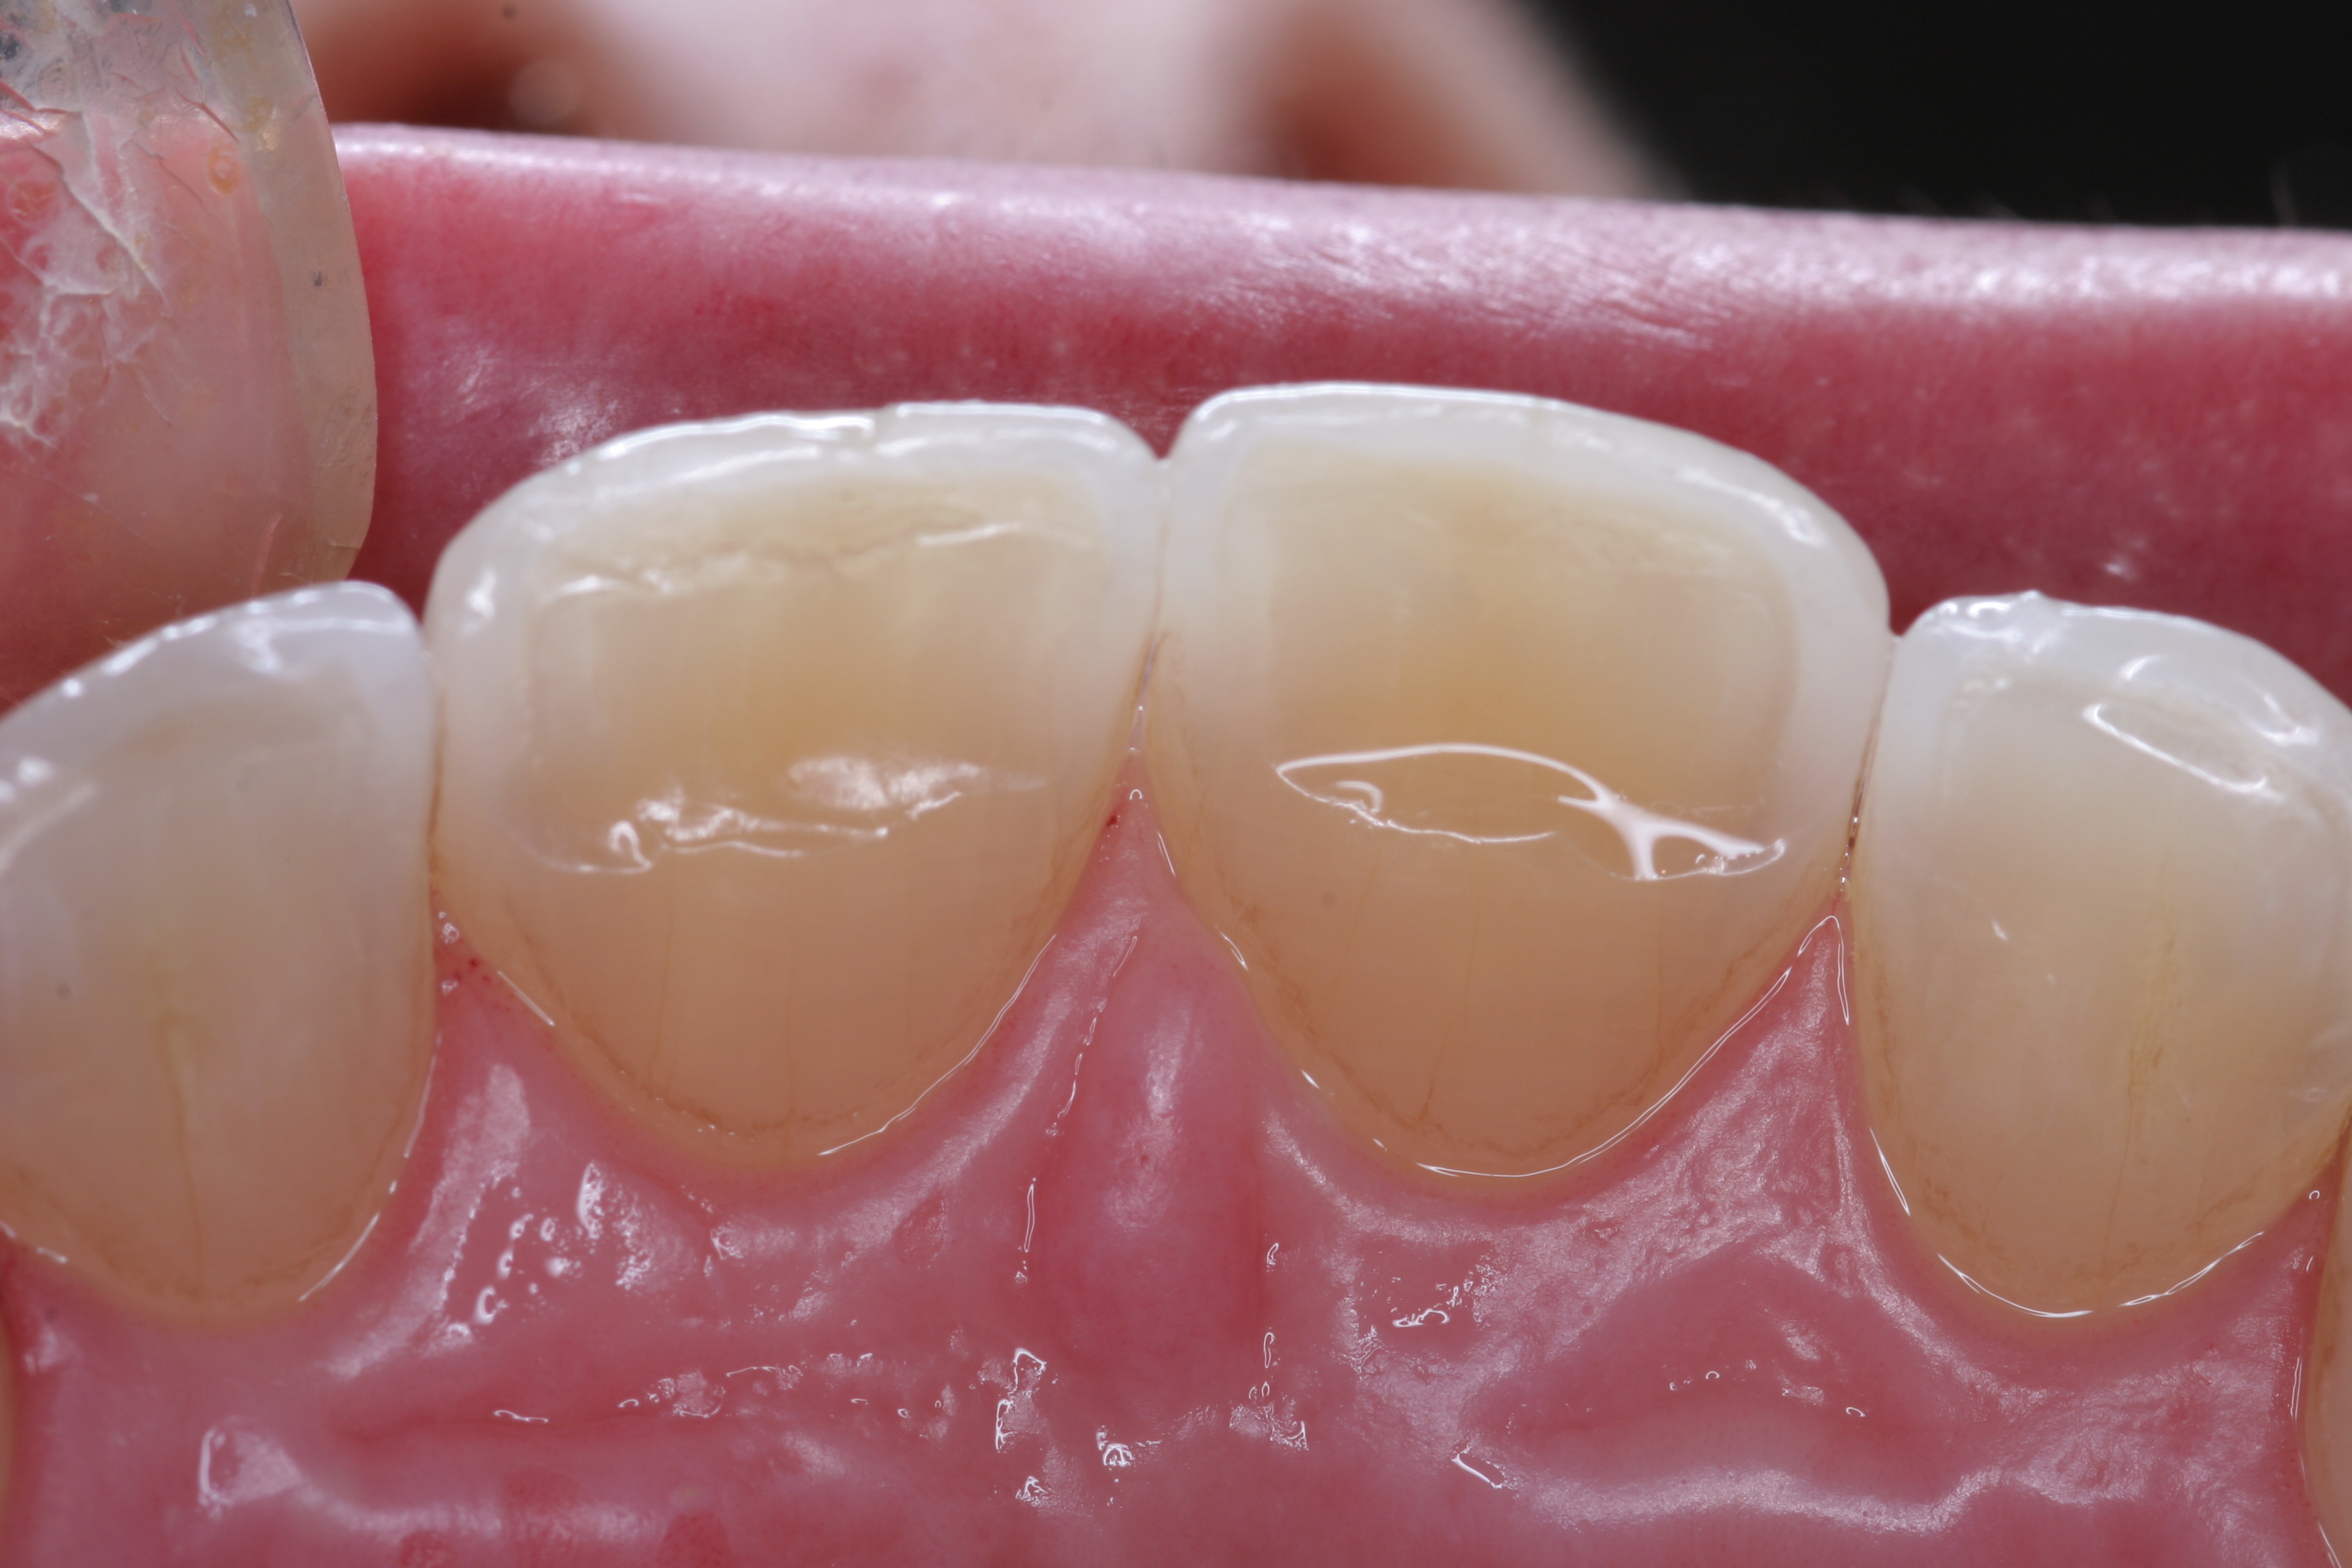

(18.) The provisional restorations show the vertical and horizontal changes in the incisal edge position.

Figure 18

(19.) The provisional restorations show the vertical and horizontal changes in the incisal edge position.

Figure 19

(20.) The provisional restorations show the vertical and horizontal changes in the incisal edge position.

Figure 20

(21.) The provisional restorations show the vertical and horizontal changes in the incisal edge position.

Figure 21